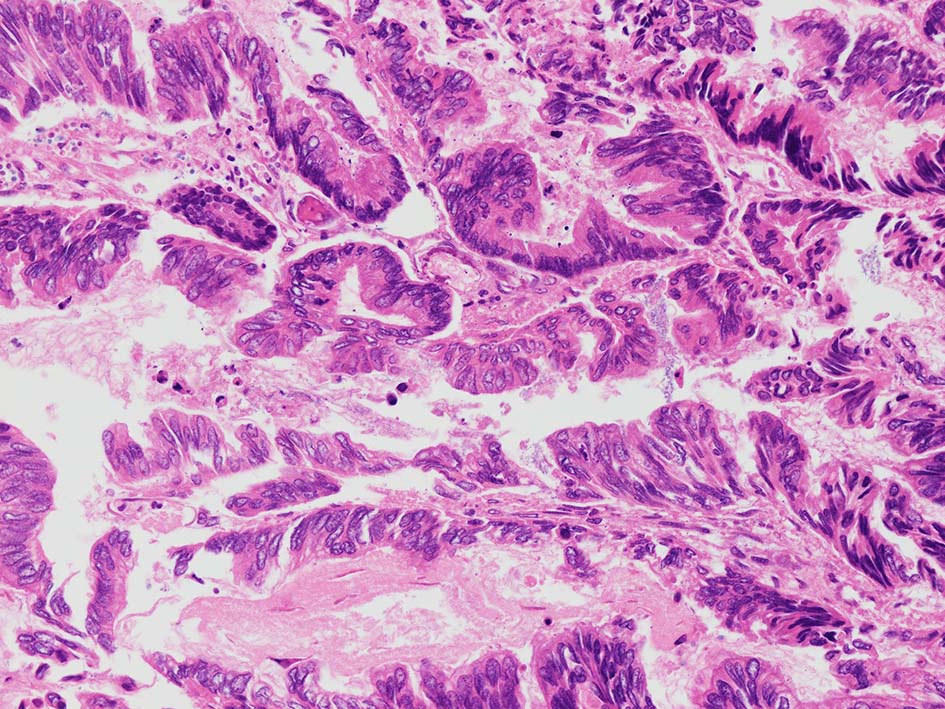

腸管型の腺癌。大腸の高分化腺癌と組織学的に区別は難しい.

desmoplastic fibrosis, 粘液浸潤のみられる組織片にはsig, porのadenocarcinoma浸潤が確認される.